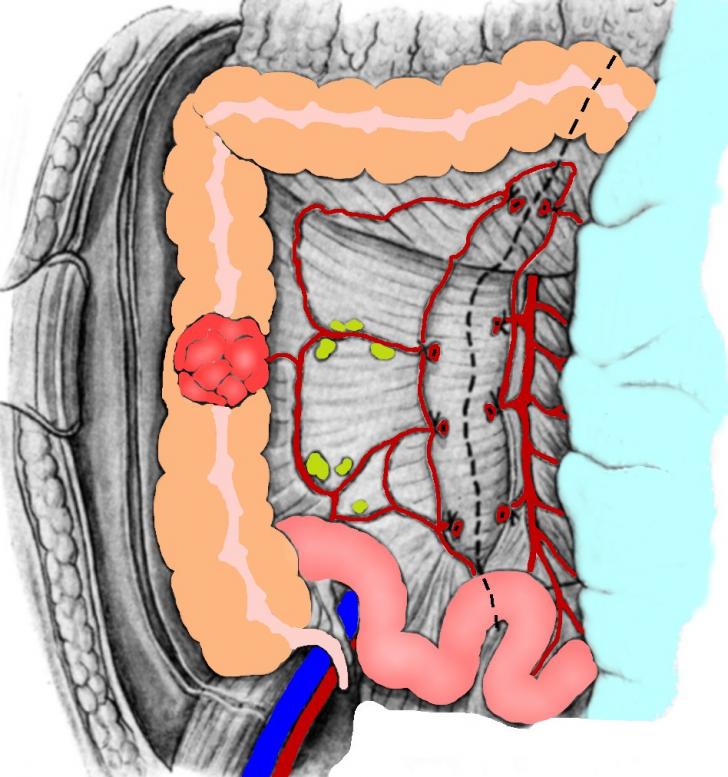

HEMICOLECTOMIA DREAPTA - CHIRURGIE

HEMICOLECTOMIA DREAPTA - CHIRURGIE I. DEFINITIE Este interventia reglata de exereza colica, prin care se extirpa ileonul terminal, ceco-colonul ascendent, unghiul hepatic, jumatatea dreapta a transversului, (vascularizate din pedicuCiteste tot ... 3421 cuvinte

Dimensiune medie

+ cu poze |